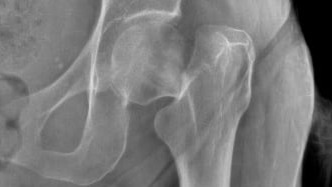

Hola, soy La Picua (Victoria) y a mis 83 años tuve una caida y me diagnosticaron fractura Transcervical del femur izquierdo y requiero de una operación e instalación de protesis para poder volver a caminar. Agradeceré enormemente su ayuda y colaboración.